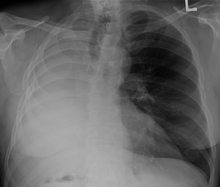

A pneumonectomy (or pneumectomy) is a surgical procedure to remove a lung. Removal of just one lobe of the lung is specifically referred to as a lobectomy, and that of a segment of the lung as a wedge resection (or segmentectomy).

The most common reason for a pneumonectomy is to remove tumourous tissue arising from lung cancer. In the days prior to the use of antibiotics in tuberculosis treatment, tuberculosis was sometimes treated surgically by pneumonectomy.

The operation will reduce the respiratory capacity of the patient; before conducting a pneumonectomy, the surgeon will evaluate the ability of the patient to function after the lung tissue is removed. After the operation, patients are often given an incentive spirometer to help exercise their remaining lung and to improve breathing function.